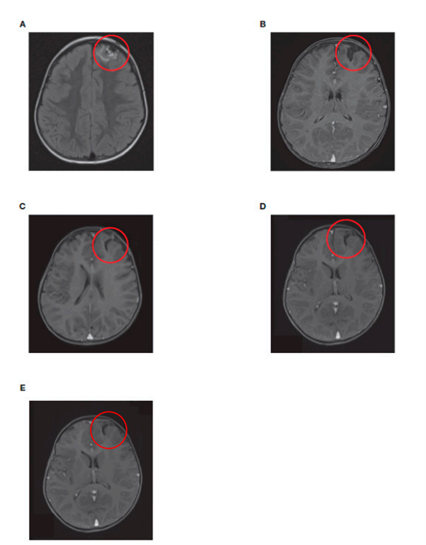

1例患者的脑部核磁共振成像扫描显示,在治疗过程中,单侧颅内前额复发病灶持续缓解(图4)。

图4. 1名CNS复发NB患者的脑部MRI扫描轴向视图显示了(A)初次复发时,(B)再诱导化疗和放疗后,(C)单倍体造血干细胞移植后,(D)达妥昔单抗β治疗完成后以及(E)单倍体造血干细胞移植18个月后的颅内左额病灶;红色圆圈显示转移病灶的位置